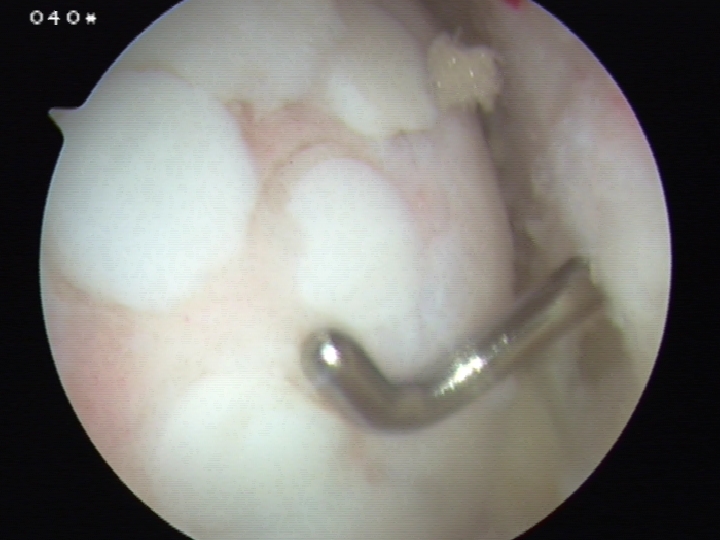

Multi-ligament knee injury (MLKI)

- 2 or more ligaments disrupted

Knee dislocation

- ACL + PCL + one of collaterals